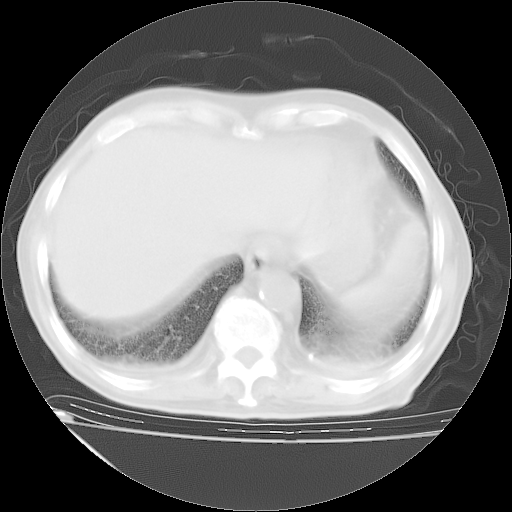

甲强龙80mg/日+抗结核治疗(异烟肼+利福霉素+乙胺丁醇)10天。复查肺部CT。

治疗10天肺部CT